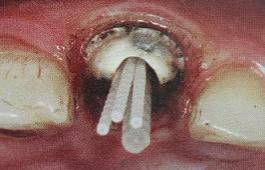

纤维桩试放时应用镊子夹持将其插入预备的根管桩道中(这涉及无菌观念和操作),就位时无阻力可稍有锢住感。

普通纤维桩对圆形截面的根管适合性较好,面对不规则时(椭圆形、喇叭形等)根管适应性差,难以取得好粘接和修复效果。

ELLIPSON 技术,采用超声预备钻对扁圆形根管进行直接预备,改善了桩核根管的适应性。有效的保存了根管牙体组织,从而增强了粘接面积,减少树脂水门汀的厚度,提高根管内纤维桩的粘接强度。